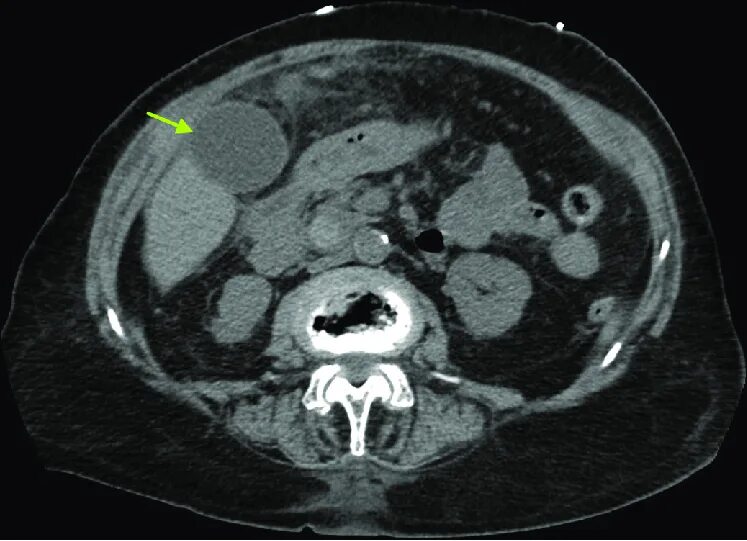

Камни в желчном мрт